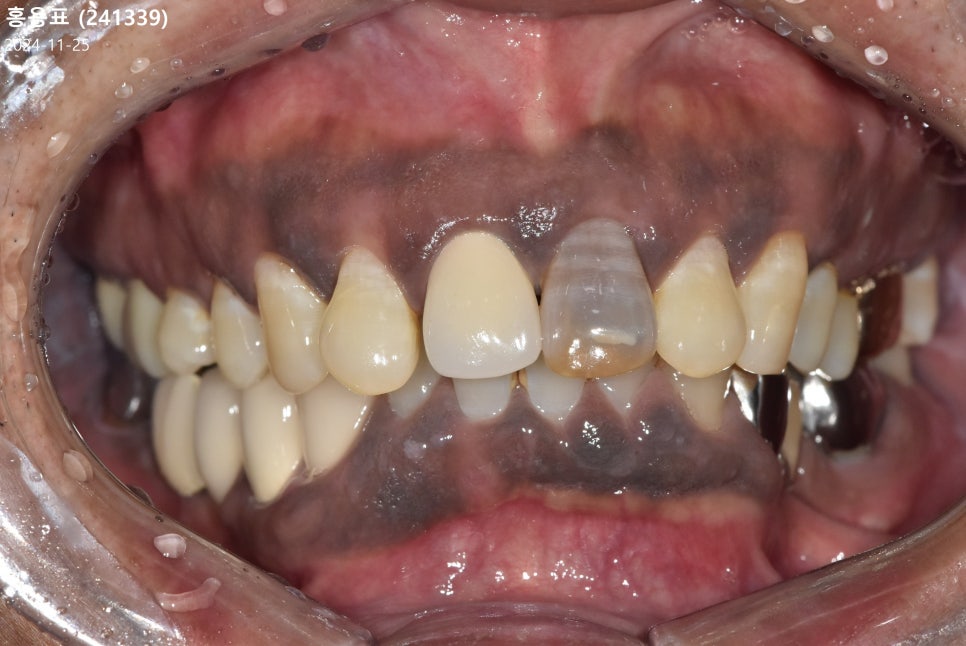

실제 최근 저희 치과를 찾으신

환자분의 사례를 말씀드릴게요.

이 환자분은 오래전 왼쪽 송곳니(#23)

신경치료를 받은 뒤 레진으로 때워서

쓰고 계셨다고 해요.

251101

시간이 지날수록

송곳니 색이 유독 어둡고

검게 변하는 것 같아 때워둔 레진에

문제가 생긴 줄 알고 내원하셨는데요.

검사 결과, 레진이 원인이 아닌

앞서 말씀드린 것처럼 신경 치료 후

내부 조직이 산화되어 내부적으로 검게 변해

비춰 보이는 것이었어요.

뿐만 아니라, 레진과 치아 사이의 미세한 틈으로

2차 충치까지 진행되고 있었기에,

더는 미루지 않고 크라운 치료를

진행하기로 했습니다.